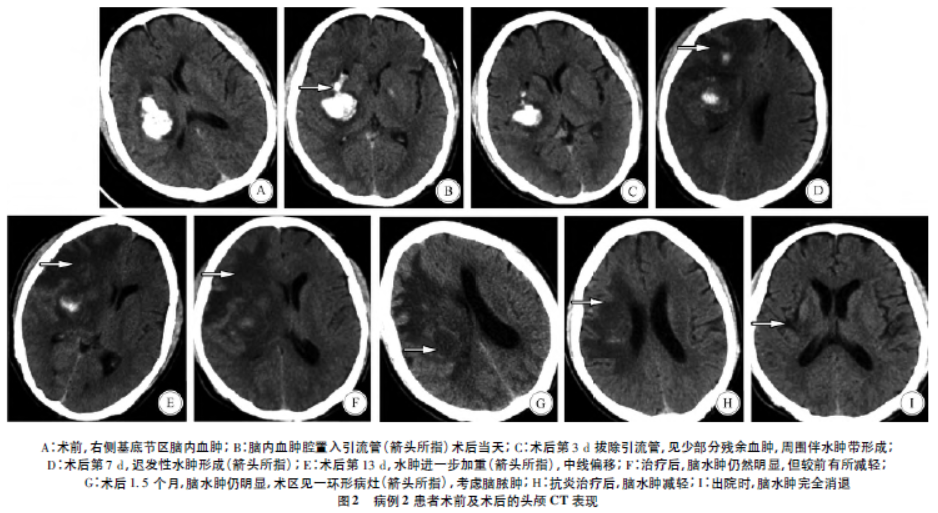

颅脑手术后迟发性脑水肿的临床分析 | 临床神经外科_医学界-助力医生

图片尺寸938x513